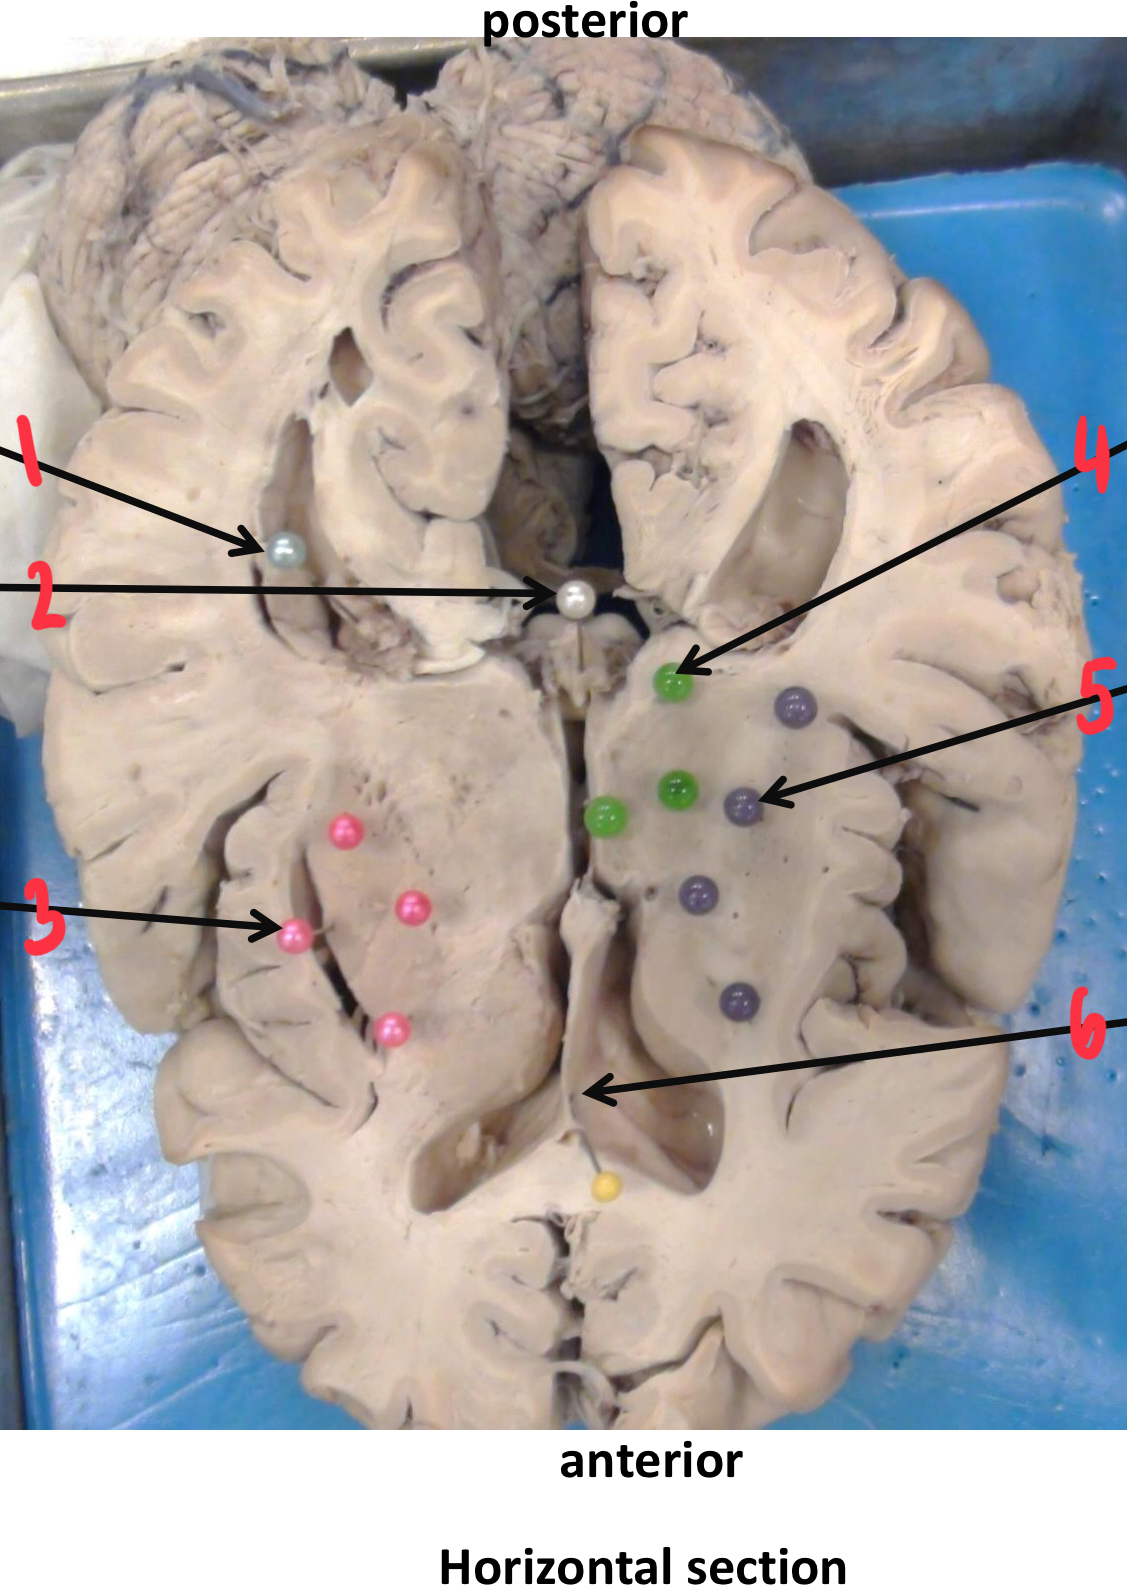

1

insula (island of Reil)

2

caudate nucleus

3

fornix

4

anterior (frontal) horn of the lateral ventricle

5

corpus callosum